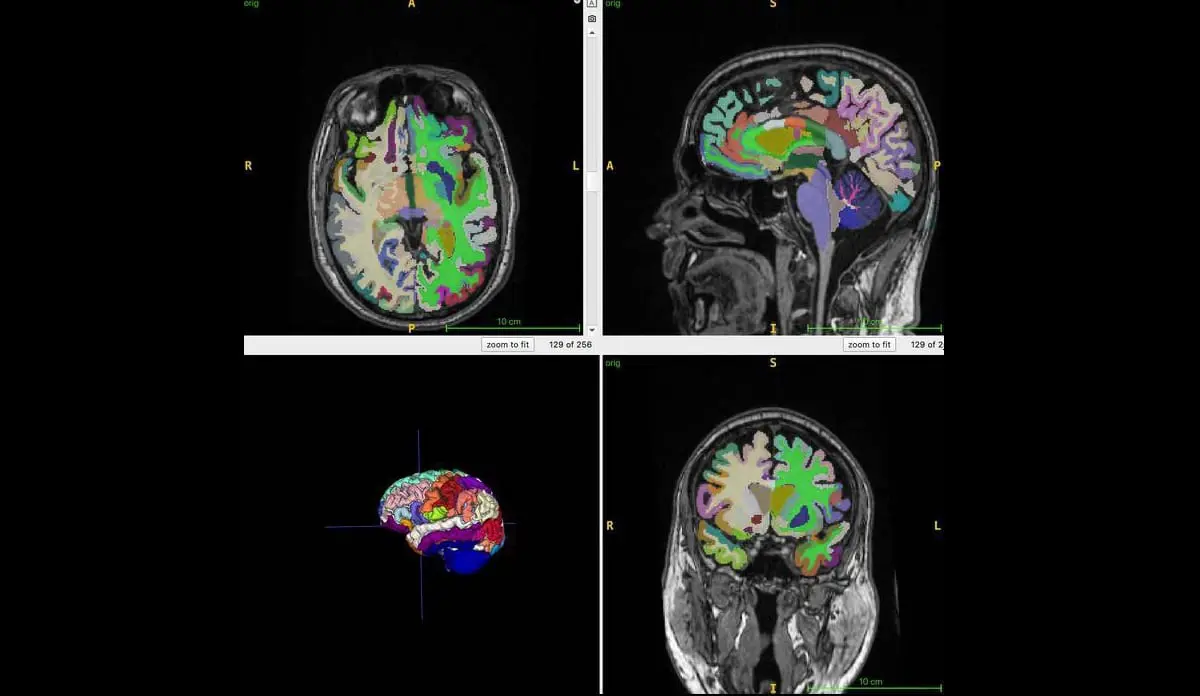

Для проведения масштабного исследования специалисты применили самые современные методы диагностики: магнитно-резонансную томографию и алгоритмы искусственного интеллекта. С их помощью детально изучались данные 1164 добровольцев средним возрастом около 55 лет, из разных медицинских центров под всесторонним и тщательным наблюдением.

Компьютерный интеллект позволил быстро и максимально точно оценить соотношение объемов мышечной массы, висцерального и подкожного жира, а также вычислить биологический возраст мозга каждого участника. В результате полученные данные показали яркую и четкую зависимость: чем лучше физический тонус и меньше вредного жира на животе — тем моложе мозг.